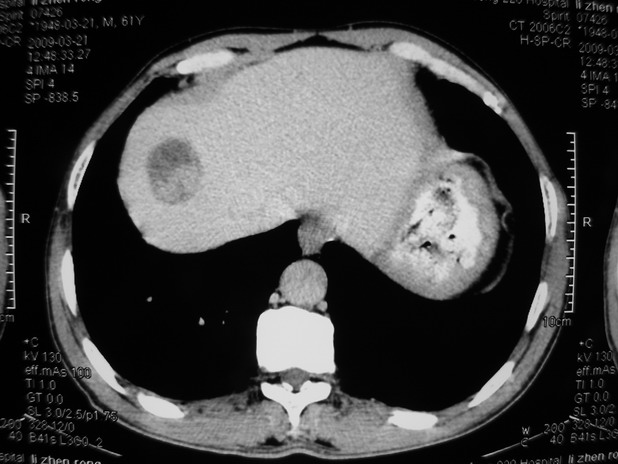

以下是引用余辉在2009-3-21 21:36:00的发言:[br]图像太乱了,建议楼主直接将强化数据按顺序列出来,病灶位置较表浅薄,有肝炎病史,灶内实性成分有显著强化,动脉期约60hu,考虑肝癌可能性大,进一步检查。